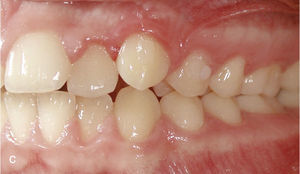

Con frecuencia los corredores vestibulares perjudican la apariencia estética al sonreír. Los dientes posteriores inclinados hacia palatino y hacia lingual «desaparecen» detrás de los dientes anteriores, de modo que la sonrisa se muestra acortada e incompleta (fig. 5a). Con el enderezamiento de los dientes posteriores combinado con una expansión se rellenan los corredores vestibulares y se completa la sonrisa (fig. 5b).